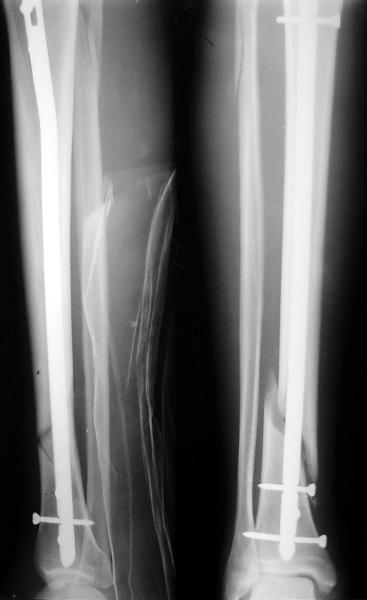

Ok. А также и следующий, в 3 месяца.

Это наглядная демонстрация возможности ранней полной нагрузки при нестабильном по оси повреждении, причем не в самых благоприятных механических условиях - при плохом сопоставлении, со слабым фиксатором.

Как я уже говорил, мы сделали выводы из этого и других подобных случаев. Очевидно, решений проблемы два - либо уменьшить нагрузку, либо увеличить прочность фиксатора. Первое решение работает не со всеми больными, так что пошли по второму пути - мы больше не используем гвозди с запирающими винтами диаметром 4 мм.

Что именно показать? Что пациент может стоять на больной ноге к 1 месяцу? При интрамедуллярном остеосинтезе по поводу ложных суставов, когда мышцы давно зажили, это и на 3-5 день наблюдается. В чем именно Вы сомневаетесь? Что гвоздь диаметром 12-13 мм с винтами более 5 мм способен нести полную нагрузку? Или что ходить без хромоты можно только после рентгенологического сращения? Или?..

12 mm intramedullary nail with tree locking (proximally 5.5mm diameter and 4.5 mm distally) screws after tree weeks can put full WB.

Мы сейчас используем бедренные гвозди 11,5 и 13 мм с винтами 6 мм, и только диаметр 10 мм - с 5 мм. Большеберцовые - для гвоздей 9 и 10,5 мм винты 5 мм, 12 мм - 6 мм. Как уже говорил, нагрузку сразу не

ограничиваем (если нет проблем с суставами).